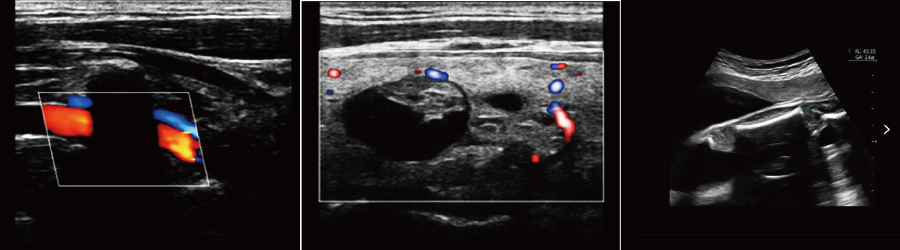

●全家族探頭應用、微米成像技術、全激活兩個探頭接口

●IMT血管內中膜自動測量

●血流M(MC)成像

強大的功能和豐富的測量軟件,迅速而便捷地幫助您解決腹部、外周血管,婦科,產科,新生兒和小兒科,骨骼肌肉,心臟等各種臨床診斷的需要;